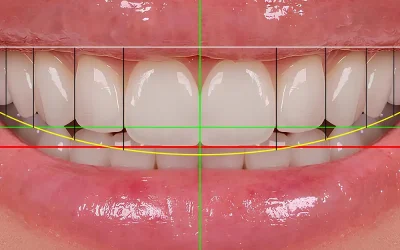

Disegnare il sorriso: i vantaggi del Digital Smile Design

Il DSD analizza il rapporto tra sorriso, labbra e volto e fornisce in anteprima il risultato finale di un trattamento. Scopri le sue applicazioni in estetica dentale.